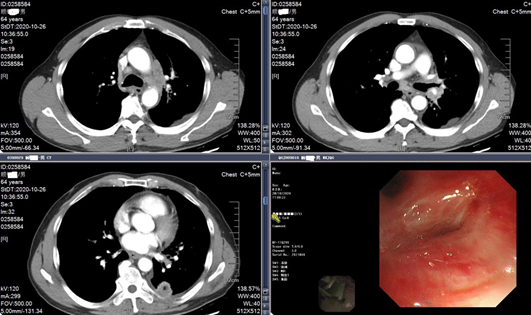

入院CT结果

■ 5天后出现急性心包积液+双侧胸水

患者从2020-11-08开始予以培美曲塞+顺铂+贝伐珠单抗+帕博利珠单抗进行治疗,5天后开始出现胸闷气喘、颈静脉怒张、听诊双肺哮鸣音、心音遥远。2020-11-16彩超提示双侧胸水,右侧中等量积液,盆腔少量积液。

2020-11-16CT结果

穿刺位置及心包积液血常规检测结果

将心包积液进行病理检测,可见腺癌细胞,初步判断为疑似腺癌超进展(即肿瘤经治疗后不但没缩小,反倒以更快的速度增长)。